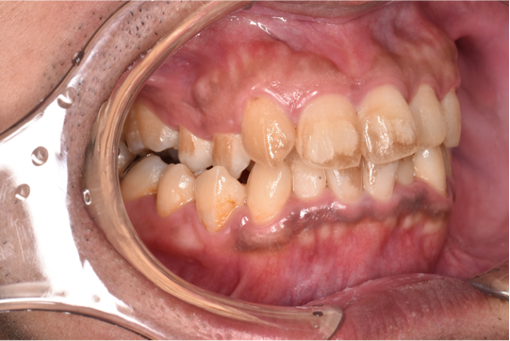

治療後

| 行ったご提案・治療内容 | ご本人はホワイトニングまで考えられていないとのことでしたので保険の範囲内での着色除去をご提案しました。 初診時に問診を行い、歯肉縁上歯石を除去後に歯面清掃を行いました。 |

| 術後の経過・現在の様子 | ご相談いただいた、歯に付着した着色を除去しとても満足いただきました。 |